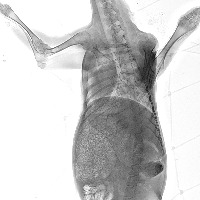

All_goat_ribs Computer Vision Project

Veterinary Diagnostics: Use this model to aid in distinguishing between various animal rib structures, specifically in the case of goats, to diagnose injuries or diseases.

Archaeological Identifications: Assist archeologists and paleontologists in identifying animal remains, verifying whether they belong to a goat based on rib structure.

Education: Enhance veterinary or biology education by providing students with a tool to study and compare different animal skeletal structures, focusing on rib cages.

Zoological Research: Contribute to zoological research and the development of comparative anatomy studies by identifying and categorizing animal bones, in particular, goat ribs.

Food Industry: Apply in the food processing and meat industry to validate the type of meat, particularly in ensuring the sourcing and representation of goat meat.